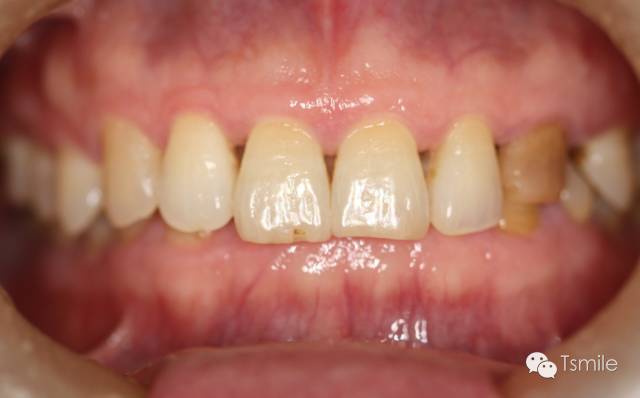

圖2: 前牙功能范圍受限導(dǎo)致的前牙重度磨耗